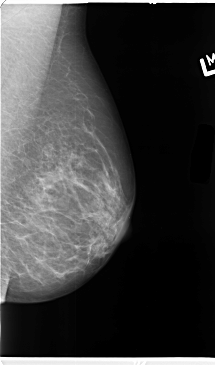

ics_version 1.0 filename B-3101-1 DATE_OF_STUDY 7 11 1996 PATIENT_AGE 48 FILM FILM_TYPE REGULAR DENSITY 3 DATE_DIGITIZED 6 2 1998 DIGITIZER LUMISYS LASER SEQUENCE LEFT_CC LINES 4632 PIXELS_PER_LINE 2632 BITS_PER_PIXEL 12 RESOLUTION 50 NON_OVERLAY LEFT_MLO LINES 4744 PIXELS_PER_LINE 2792 BITS_PER_PIXEL 12 RESOLUTION 50 NON_OVERLAY RIGHT_CC LINES 4720 PIXELS_PER_LINE 2472 BITS_PER_PIXEL 12 RESOLUTION 50 OVERLAY RIGHT_MLO LINES 4696 PIXELS_PER_LINE 2640 BITS_PER_PIXEL 12 RESOLUTION 50 OVERLAY |